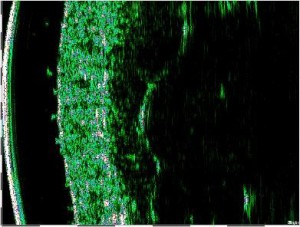

-Υπέρηχος Υψηλής Συχνότητας (HFUS) και Ιστολογία

-Μέτρηση επιπέδων Breslow και Klark σε έμβιο οργανισμό (IN VIVO)